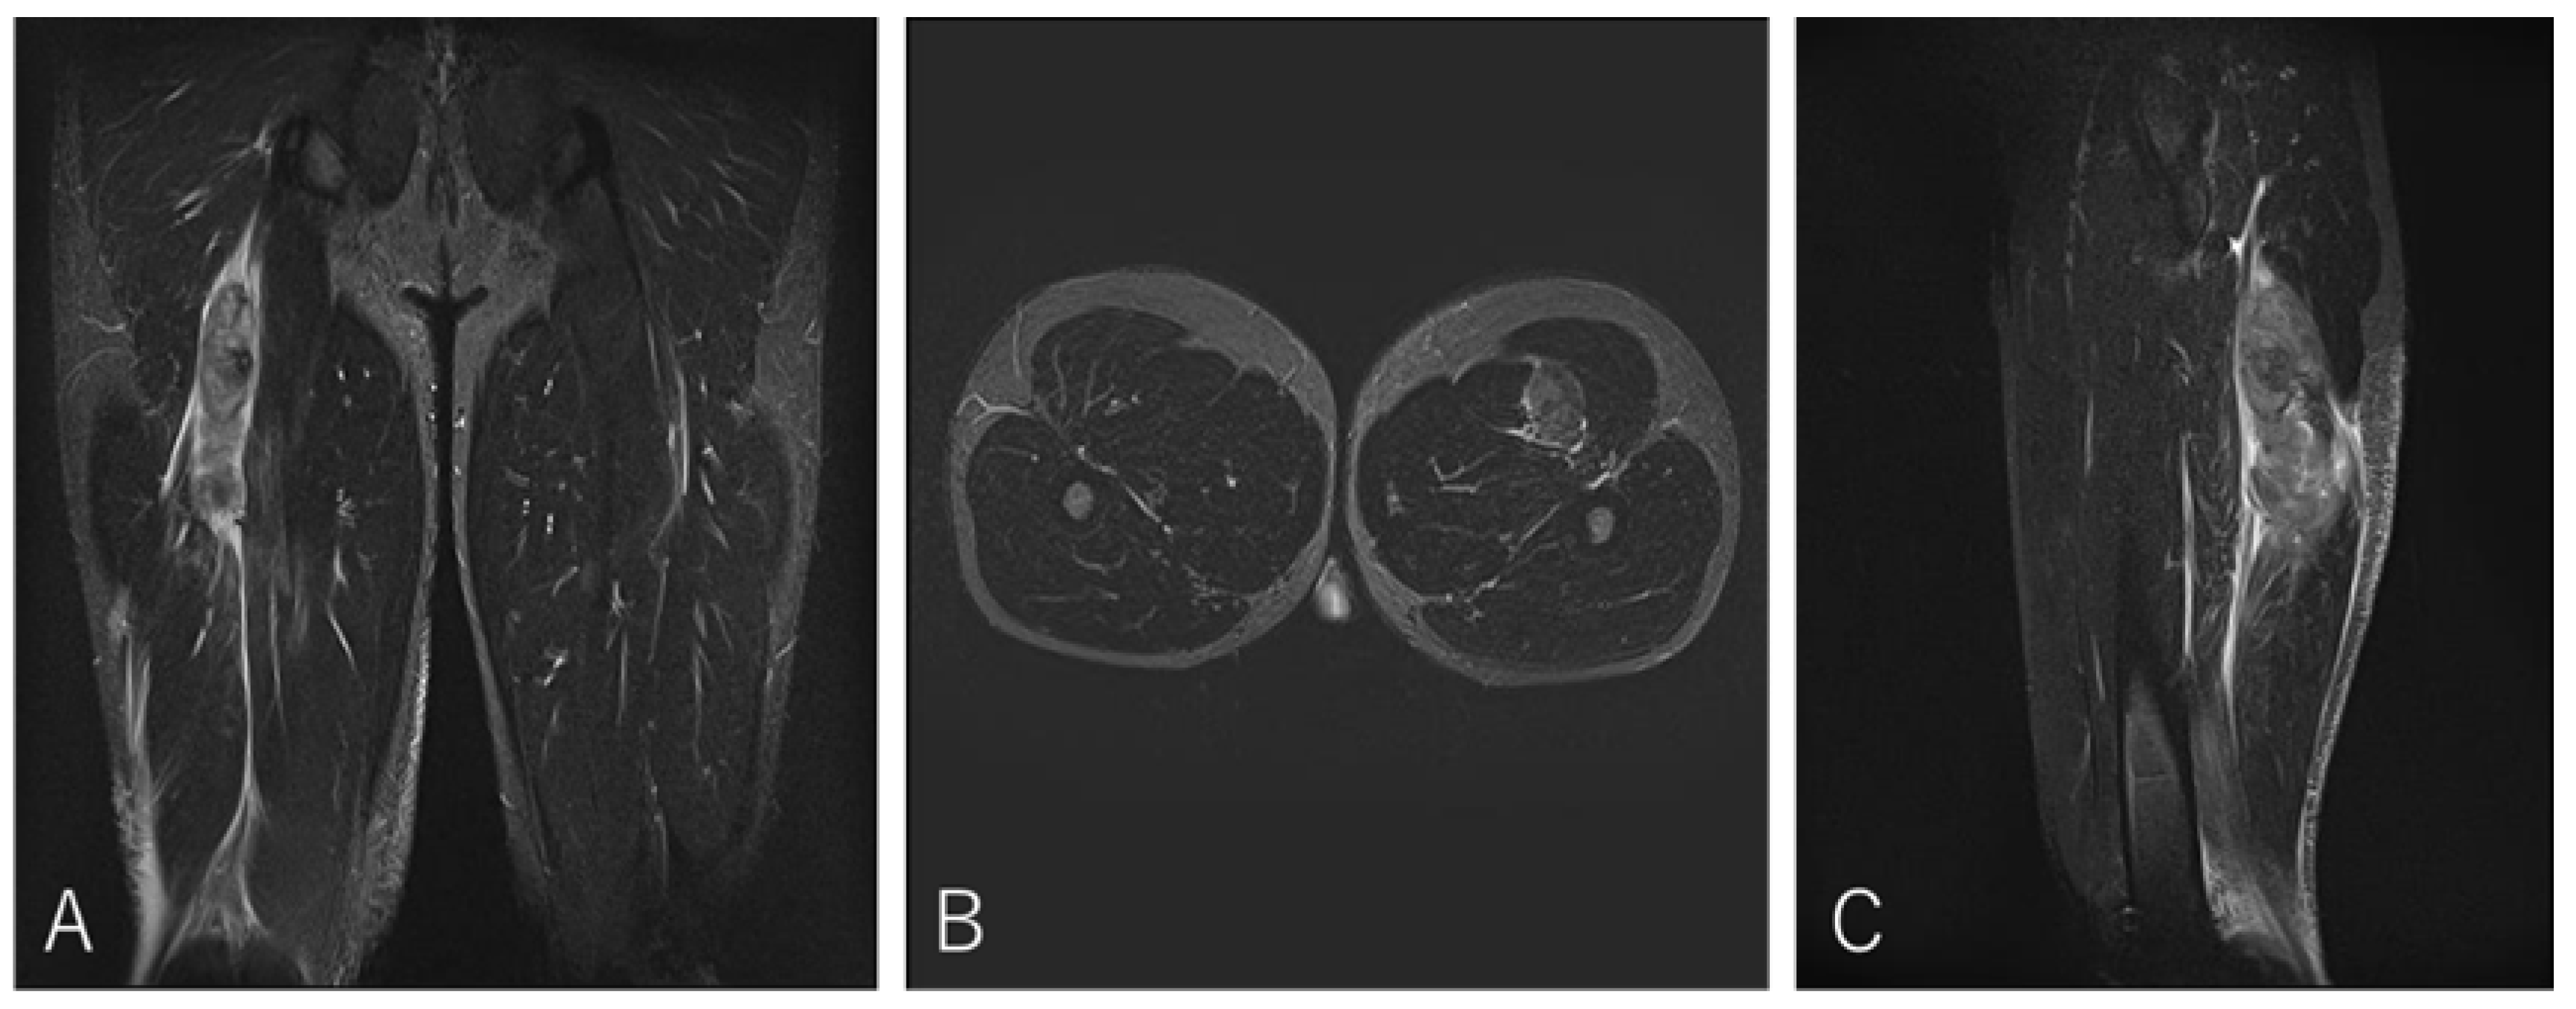

4.1. Case 1. Type I / Zone A (Conjoint tendon detachment), Grade 2

A 20-year-old lock (FW) stepped to evade an opponent while running with the ball and experienced a sharp tearing sensation in the posterior thigh near the origin. He returned to competition after 20 weeks.

Figure 3. Case 1 MRI images: Conjoint tendon detachment, Type I.

Preprints 186662 g003